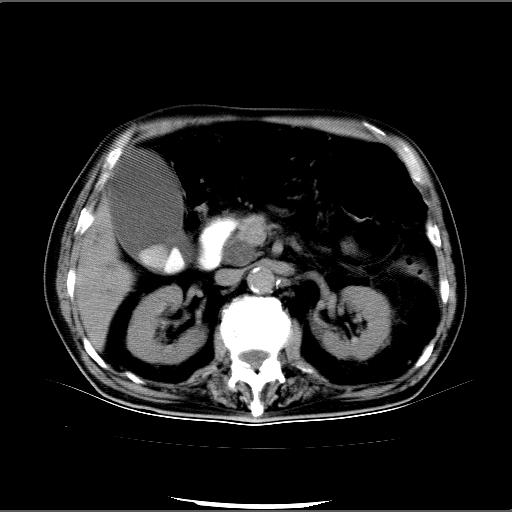

患者男82岁,黄染,发热10天,无腹痛。

1胆总管下端结石伴肝内外胆管扩张;2胆囊颈部结石伴胆囊积液

胆囊多发结石,胆囊积液;胆总管中下段结石,中上段扩张。

胆总管下段结石伴胆道系统扩张;胆囊炎伴胆囊结石.

有时胆总管下段结石的密度并不是均匀的高密度,而是以高密度为主的伴中心等密度的混合物,这与胆道结石的多样性有关,少数时候诊断困难时应结合临床病史,症状等,还有增强扫描都可以帮助明确诊断!!常与胆道蛔虫伴钙化鉴别!

1、胆总管壶腹部结石并胆总管、胆囊及肝内胆管扩张。2、胆囊多发结石。3、两下胸膜局限性增厚。4、胃体部大弯侧胃壁稍厚,建议:多量饮水后增强ct扫描除外占位性病变。

此病例有结果了:患者术后为:胆总管下段结石伴胆道系统扩张;胆囊炎伴胆囊结石。

各位战友分析的都很正确,是一个典型的病例。